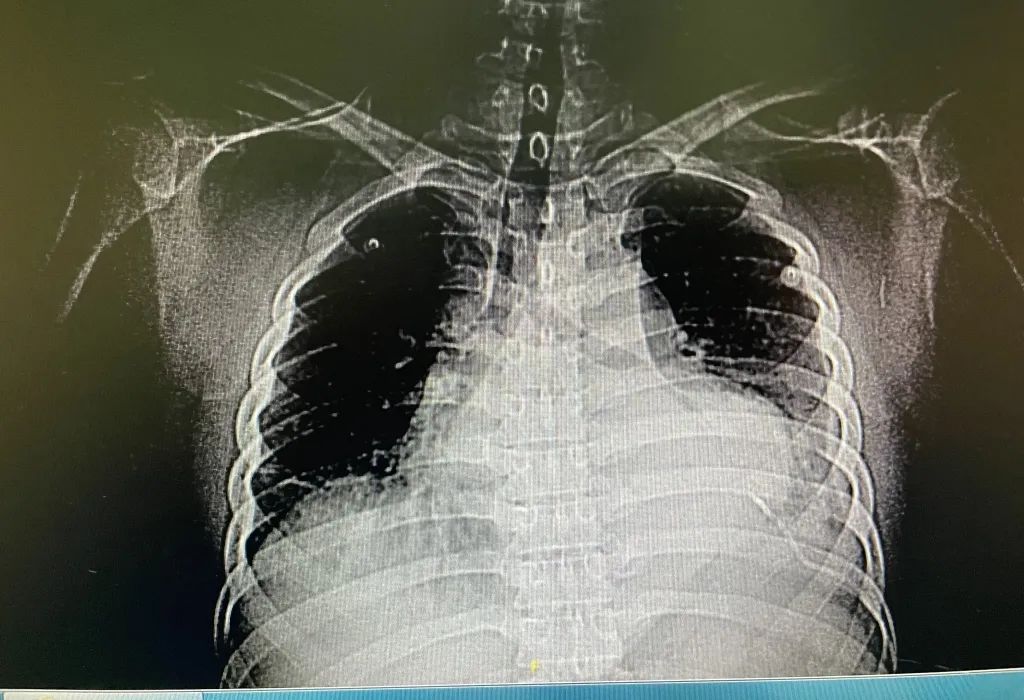

患者针扎破心脏引起大量心包积液

复查胸部ct和心超后显示,针已经跑到了心脏里面,造成了心脏破裂伤,伴有心包大量积血,心包填塞,高血压3级(极高危),需要立即进行手术。